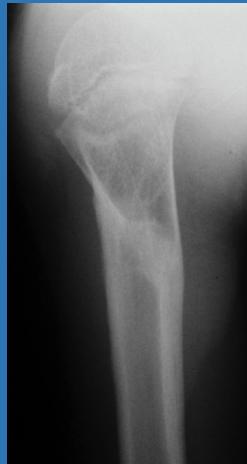

| Dynamic Hip Screw (DHS) | Indications: Fixation of intertrochanteric fractures. | ![]() |

| Inter-locking Nail | Indications: Fractures of long bones. Advantages: Minimally invasive, preserves fracture hematoma, allows early weight-bearing on lower limb. | , , , ![]() |